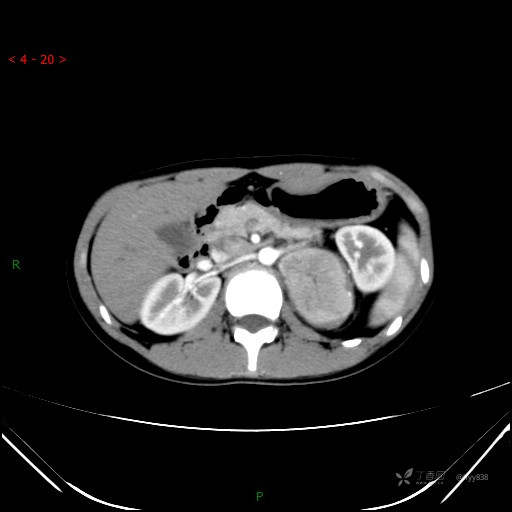

增强静脉期